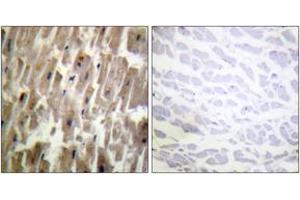

CRYAB 适用: 大鼠, 小鼠 ELISA, IHC (p), ICC, IF (cc), IF (p), IHC (fro) 宿主: 兔 Polyclonal unconjugated